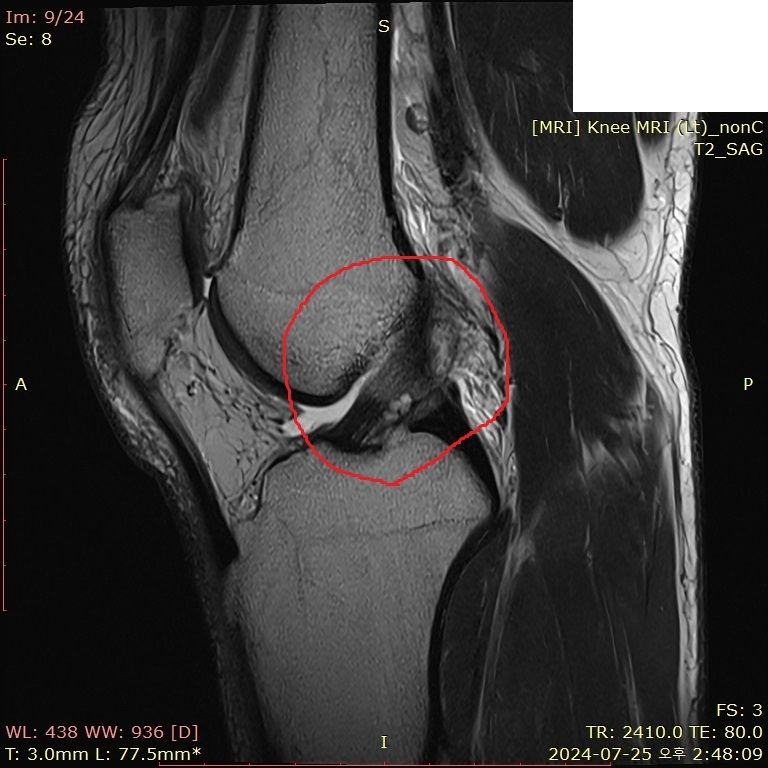

무릎 부딪혔는데 mri 한번 봐주시면 감사하겠습니다..

뛰다가 넘어졌습니다.. 예전에는 무릎이 부어도 병원 안 갔는데, 최근에는 중요성을 알아서 미리미리 검진 받자는 의미로 갔다왔습니다

• 1번 째 사진

보여주신 MRI만 보면 전방, 후방 십자인대 손상이 의심되지 않습니다.